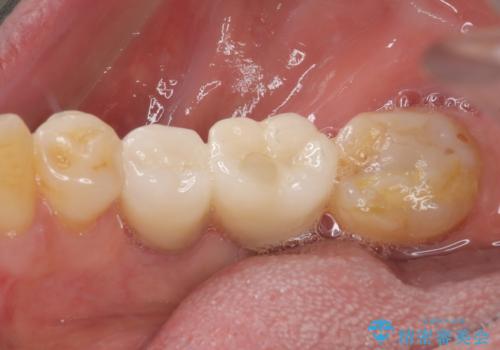

インプラント埋入時に植立具合の安定性を測定したところ、十分な数値が得られたため、速やかに仮歯を装着して咬合回復をさせることができました。

外科処置を1回に抑えることができ、あっという間に治療を終えることができました。